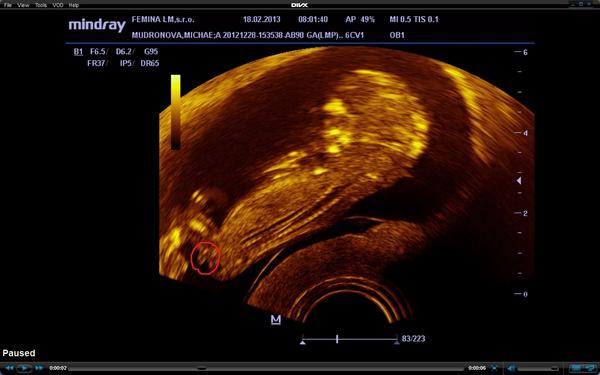

@deniska84 toto je z 12tt minule ked som bola robil mi sono a nevideli sme nič, lebo malé bolo otočené chrbátikom, len nerozumiem tomu prečo mi minule nepovedal čo to bude, ked to bolo pekne vidieť, asi sa viac sústredil na nosovú kostičku lebo sa stále hýbalo a ja som sa na pohlavie ani nepýtala, len teraz